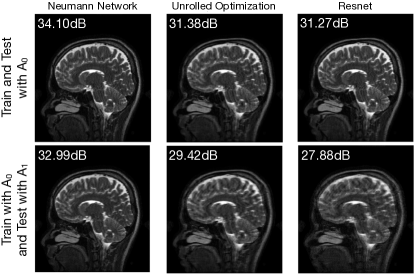

Robustness to different forward model at test time than at train.

In some settings, the forward model used during training is different from the forward model used during testing. For example, imagine learning to reconstruct MRI images for a scanner at one clinic and then attempting to use that learned algorithm to reconstruct MRI images for a (subtly different) scanner at another clinic. The different methods described in Section 4 will have different degrees of robustness to perturbations in the forward models between training and testing. This is illustrated in Figure 11 for a few representative methods.